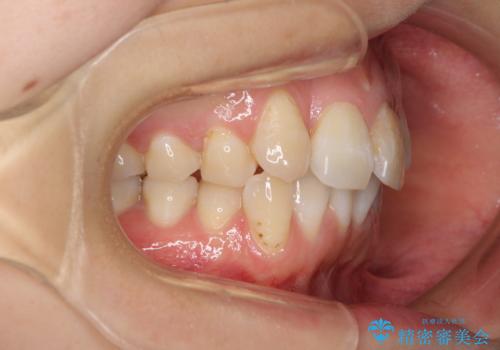

内側にある歯が邪魔 重なった前歯の歯列矯正

- 重なった前歯を邪魔に感じ、汚れも溜まりやすいことを気にして来院された患者様です。

右上前から2番目の歯が内側に転位しているため、上顎の正中は右にずれていました。